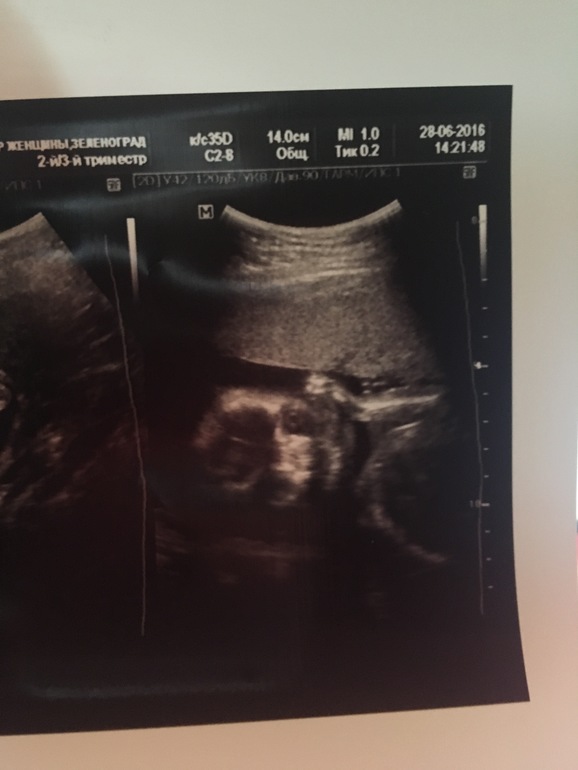

Узи 21 неделя

УЗИ, КТГ, доплерВсем привет девочки) на скрининге не смогли толком пол определить, из за того что ножки поджал и все спрятал. И сказали что даже похоже на девочку. Я не выдержала сходила на платное узи) мальчик)))

Все с ним хорошо, растёт, развивается, 360 гр( не много ?) сердечко 152 удара. Бпр 50 мм. Фото приложу

( лицом к нам лежит и видно глазки, рот, ручку)